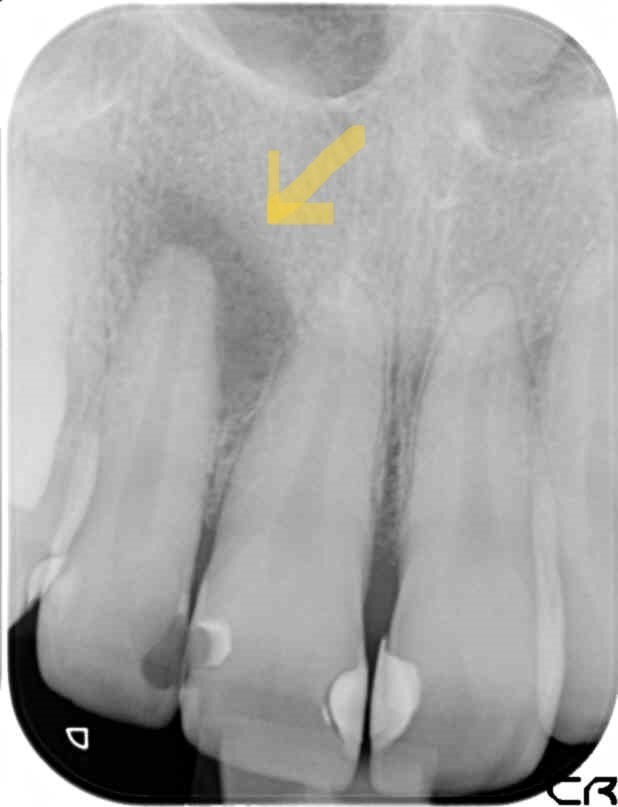

過去に根管治療した歯の再発 : 再根管治療

術前

根管に再治療(過去に根、神経の治療をしたところに再び症状がでている)の場合には、とくにマイクロスコープは必須と考えております。その成功率は病変の大きさや本来の根管の形が維持されているか、いつどのような方法で行われたか等の条件によって大きく変わりますが、平均70%前後といったところでしょうか。いずれにせよ再発したその歯には初回治療時になにかうまくいかなかった原因があるはずです。たとえば、極端に曲がった根で、物理的、技術的に感染が取り切れないような形態の場合、根に穴があいていて感染を封じ込められない場合、レントゲンやCTにて確認できないようなひびや破折線が存在している場合もあります。